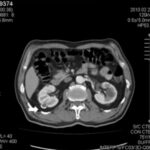

La Categoría IV presenta captación de un componente sólido intra quístico, muestra realces nodulares fuera de la pared y de los septos interpuestos en el área quística compleja, calcificaciones gruesas, vascularizadas con un importante realce con contraste yodado IV. En realidad, son lesiones malignas con componente quístico. Se trata de neoplasias quísticas, y precisan cirugía y estadificación.(19, 21) (Anexos 11 y 12).